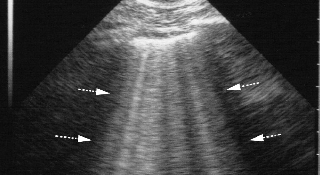

С помощью УЗИ легких можно прогнозировать тяжесть коронавирусной пневмонии

В новости описана точка отсечения на УЗИ легких для прогнозирования тяжести коронавирусной пневмонии...